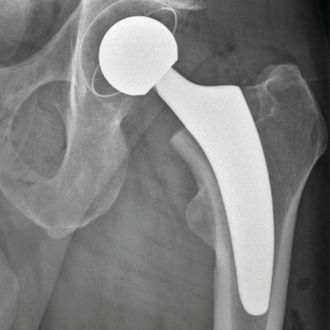

Hüftendoprothetik

Minimalinvasive Operationstechniken ermöglichen einen schonenden Hüftgelenkersatz – für eine schnellere Genesung und mehr Mobilität im Alltag.

Röntgenaufnahme eines Hüftgelenks mit eingesetzter Hüftprothese.